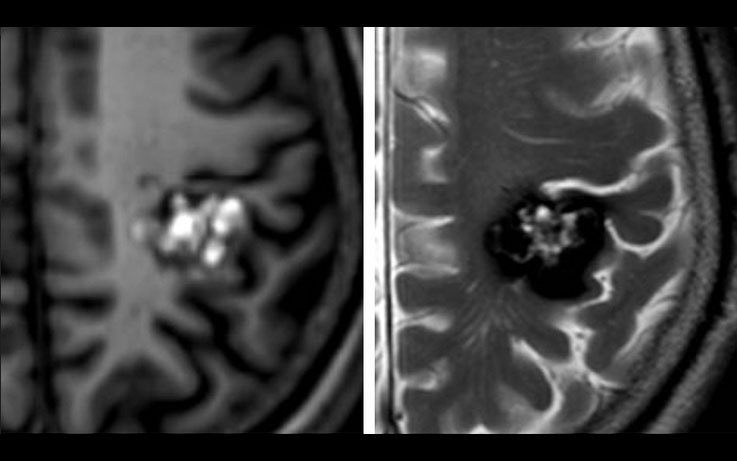

•  Cavernous Malformation

We specialize in the most challenging and symptomatic cavernoma cases:

•  Cavernomas causing recurrent hemorrhage

•  Cavernomas causing drug-resistant seizures

•  Brainstem cavernomas (high-risk locations)

•  Spinal cord cavernomas

•  Cavernomas in eloquent brain regions